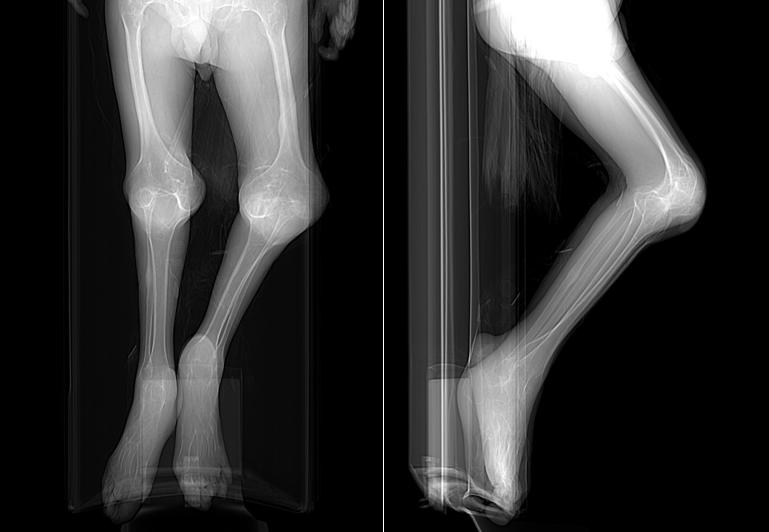

△ 患者术前站位、坐位、卧位、刷牙及影像视频

术前双髋关节X线图片